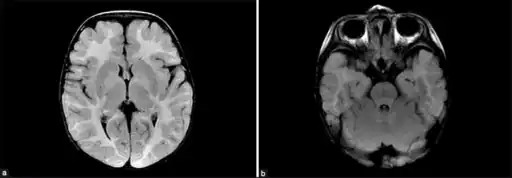

MDDS is diagnosed based on systemic symptoms presenting in infants, followed by a clinical examination and laboratory tests (for example, high lactate levels are common) medical imaging, and usually is finally confirmed and formally identified by genetic testing.[5]

SUCLA2 and RRM2B related forms result in deformities to the brain.[5] A 2007 study based on 12 cases from the Faroe Islands (where there is a relatively high incidence due to a founder effect) suggested that the outcome is often poor with early lethality.[17] More recent studies (2015) with 50 people with SUCLA2 mutations, with range of 16 different mutations, show a high variability in outcomes with a number of people surviving into adulthood (median survival was 20 years). There is significant evidence (p = 0.020) that people with missense mutations have longer survival rates, which might mean that some of the resulting protein has some residual enzyme activity.[2]